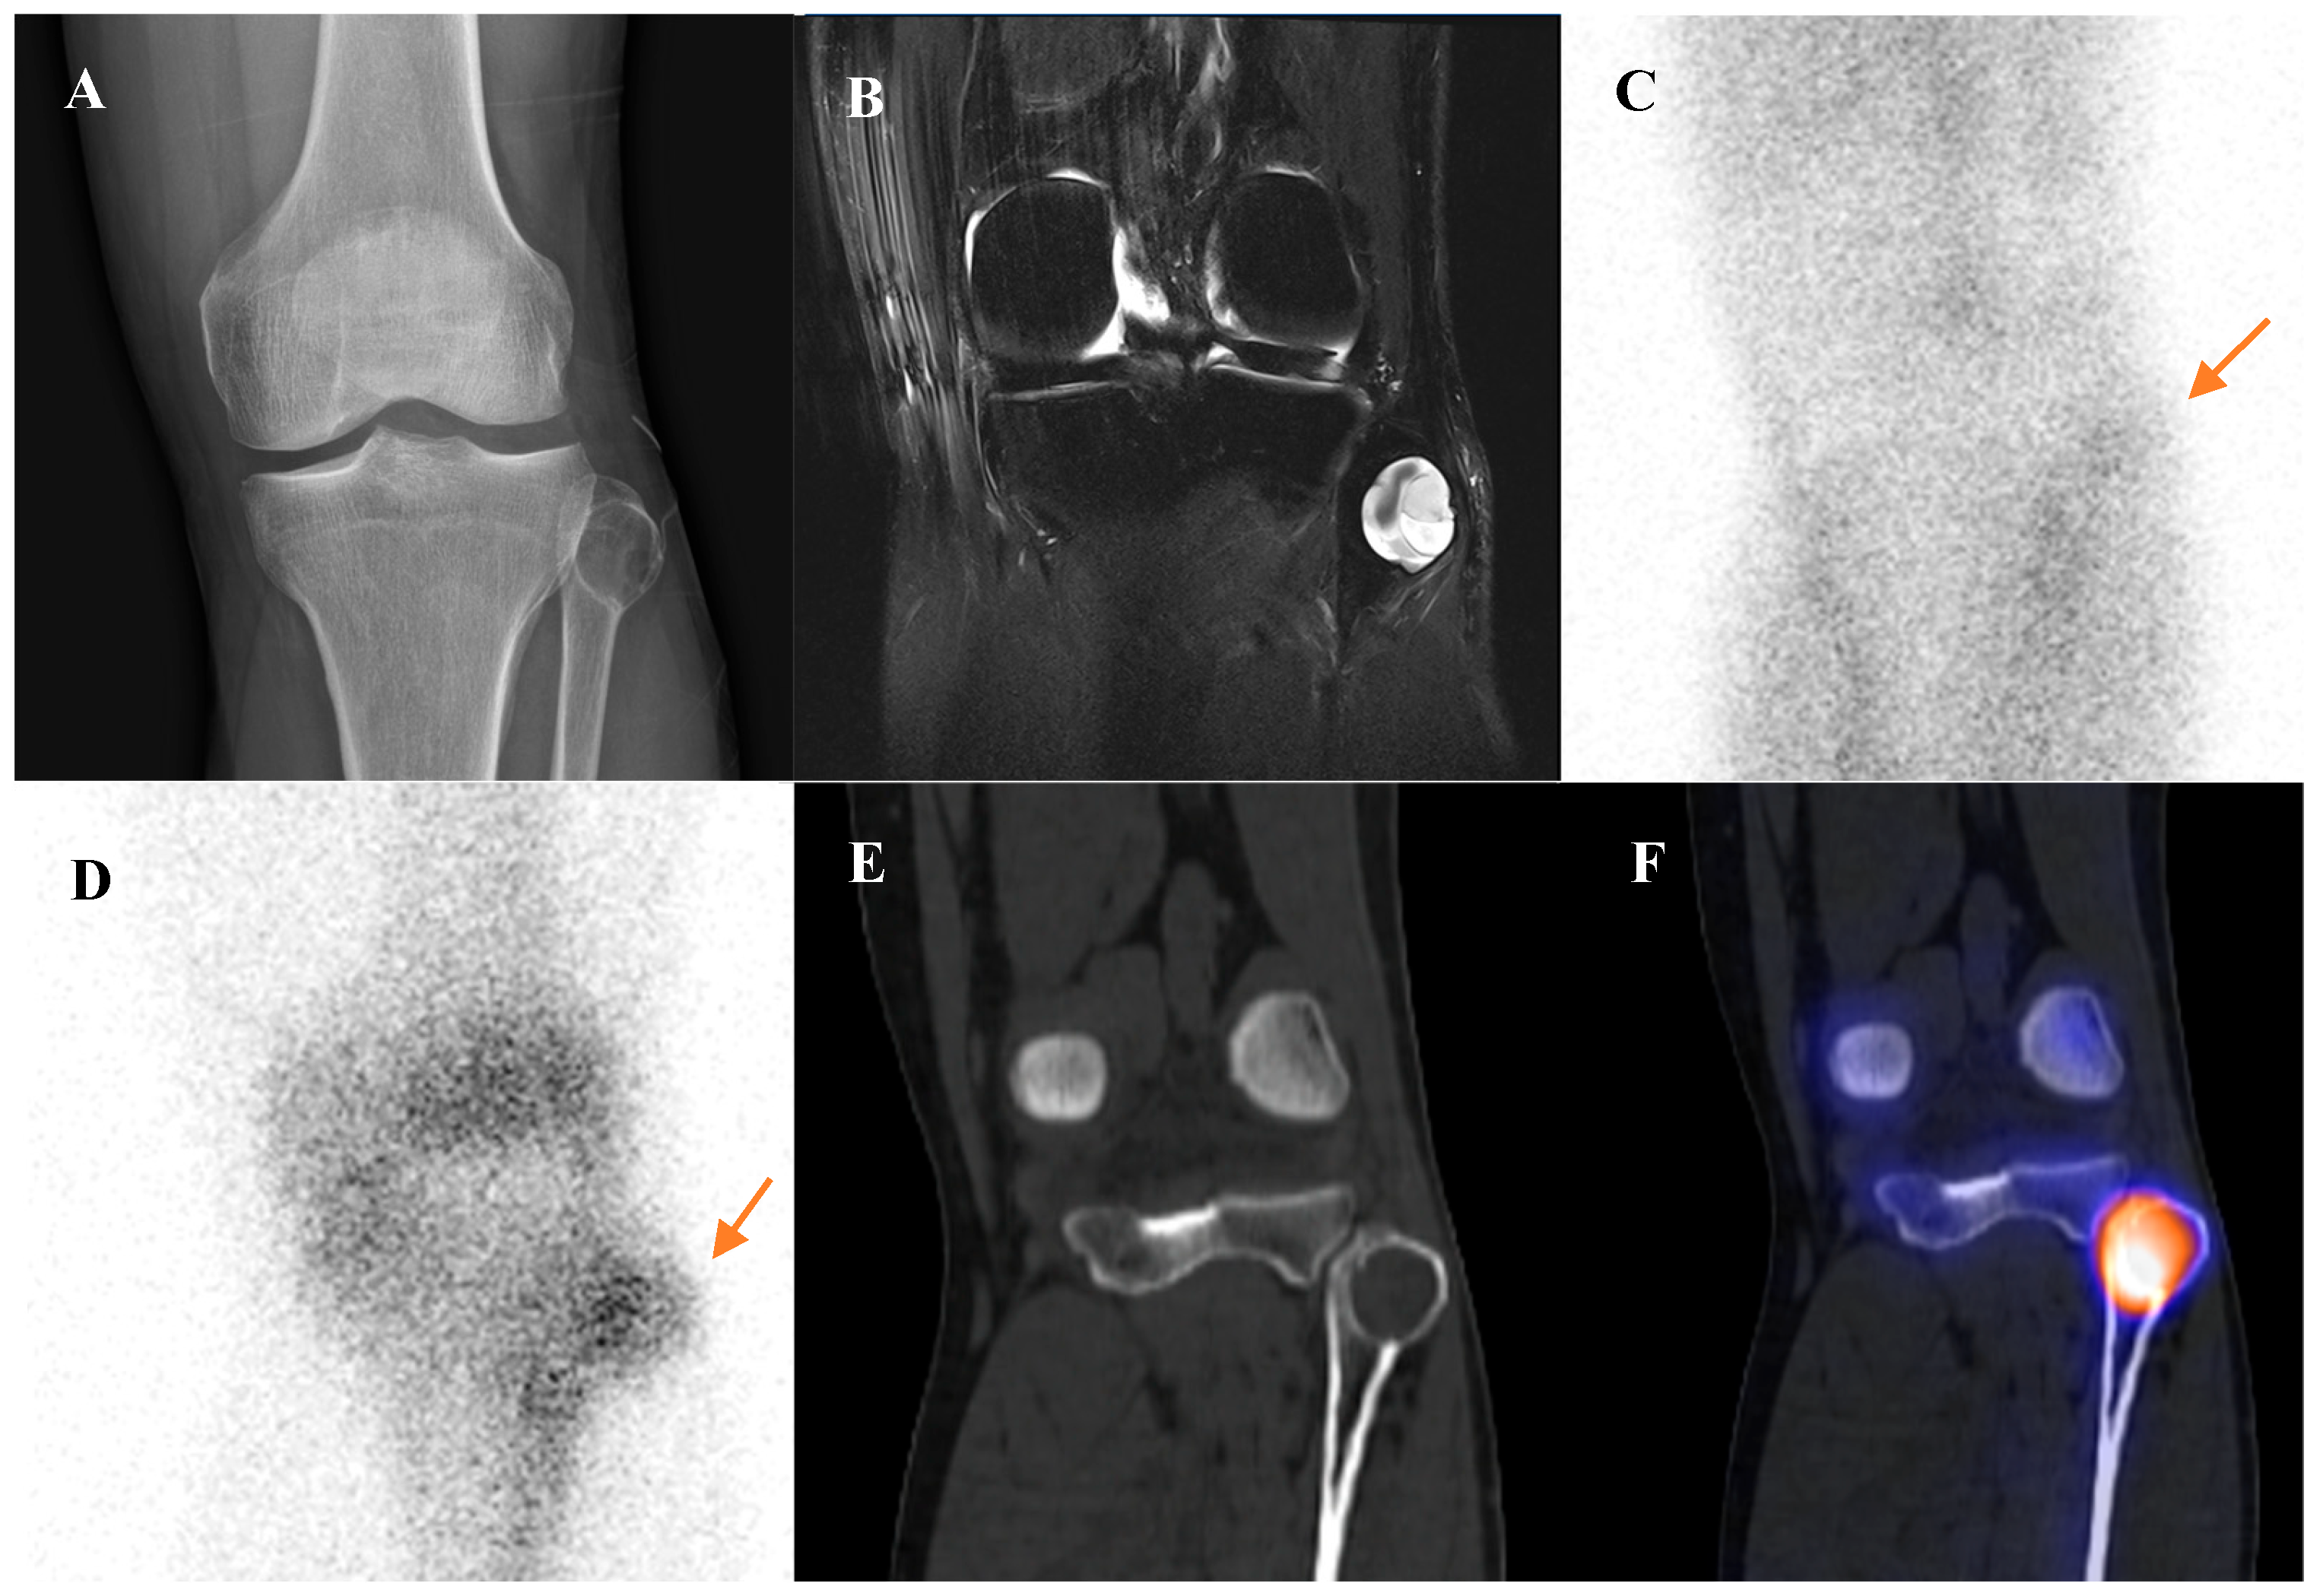

Chondroblastoma is a rare, benign cartilaginous tumor that characteristically arises in the epiphysis of long bones in adolescents and young adults [3,75]. Similarly to osteoblastoma, chondroblastoma is a significant mimic of malignancy on functional imaging. It is a metabolically active tumor that demonstrates intense uptake on both bone scintigraphy and [18F]FDG PET/CT [76,77]. Figure 7 demonstrates such a case, showing a chondroblastoma of the femoral greater trochanter with cortical disruption, extraosseous extension, and increased uptake on both bone scintigraphy and [18F]FDG PET/CT. The key to differential diagnosis is context: the combination of its classic epiphyseal location in a skeletally immature or young adult patient, along with its characteristic radiographic appearance (a lytic lesion with a thin sclerotic rim), should strongly suggest chondroblastoma despite the high metabolic activity [78]. Although metastasis from chondroblastoma is exceedingly rare, the whole-body survey capability of bone scintigraphy and [18F]FDG PET/CT may still be considered valuable in comprehensive staging and in the rare detection of distant involvement [79,80,81].

Figure 7.

A 22-year-old male with chondroblastoma of the right femoral greater trochanter. (A) Bone scintigraphy shows focal uptake. (B) T2 fat-suppressed magnetic resonance imaging reveals an osteolytic mass with cortical disruption, extraosseous extension, fluid–fluid levels suggesting hemorrhage, nodular rim enhancement, and peritumoral edema, mimicking a malignant tumor with secondary aneurysmal bone cyst. (C,D) Bone single-photon emission tomography/computed tomography (CT) demonstrates a well-defined osteolytic lesion with a sclerotic rim and intense uptake at the site of extraosseous extension. (E,F) [18F]FDG positron emission tomography/CT shows intense uptake (SUVmax 9.8) at the lesion site. Surgical excision confirmed chondroblastoma with secondary aneurysmal bone cyst change.